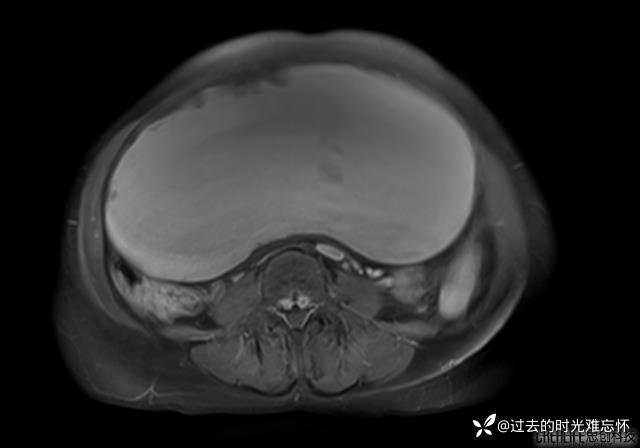

腹大能容5000液;术后腹部好轻松。妙手回春有结果。公布结果。

患者性别:女

患者年龄:65岁

主诉: 发现腹部隆起半年余。无其他明显不适。

浆液性囊腺瘤 (22)